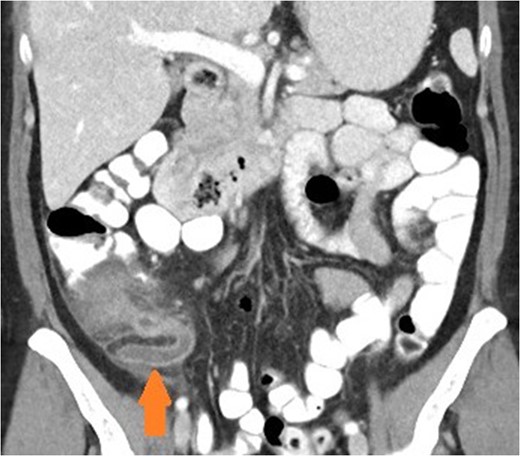

Axial view of patient with caecal carcinoma. Eccentric caecal wall thickening with homogenous contrast enhancement (arrow). Mild pericolic fat stranding is present.

There are a number of CT features that help distinguish bowel wall thickening from malignant and benign causes [3]. A neoplastic cause is suggested if there is focal bowel wall thickening (less than 5 cm of extension) which is typically asymmetrical and eccentric. These may have homogeneous contrast enhancement due to infiltration of a tumour mass, or a heterogeneous areas of low attenuation from ischaemia and necrosis, findings with a sensitivity of up to 97% [4]. Malignancy may also have shouldered edges as opposed to tapering transition to normal bowel wall. Appendiceal dilatation, if present, may be thin walled and without inflammatory stranding due to a gradual obstructive process, although appendicitis can be a presenting symptom for carcinoma. Regional lymphadenopathy and distal metastases, when present, support the diagnosis.